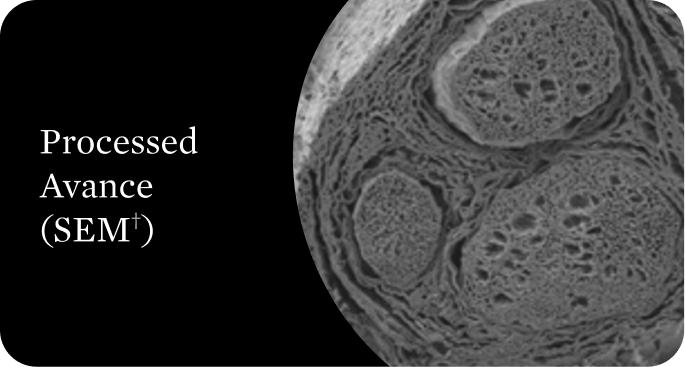

Avance® (acellular nerve allograft–arwx) is now FDA approved!